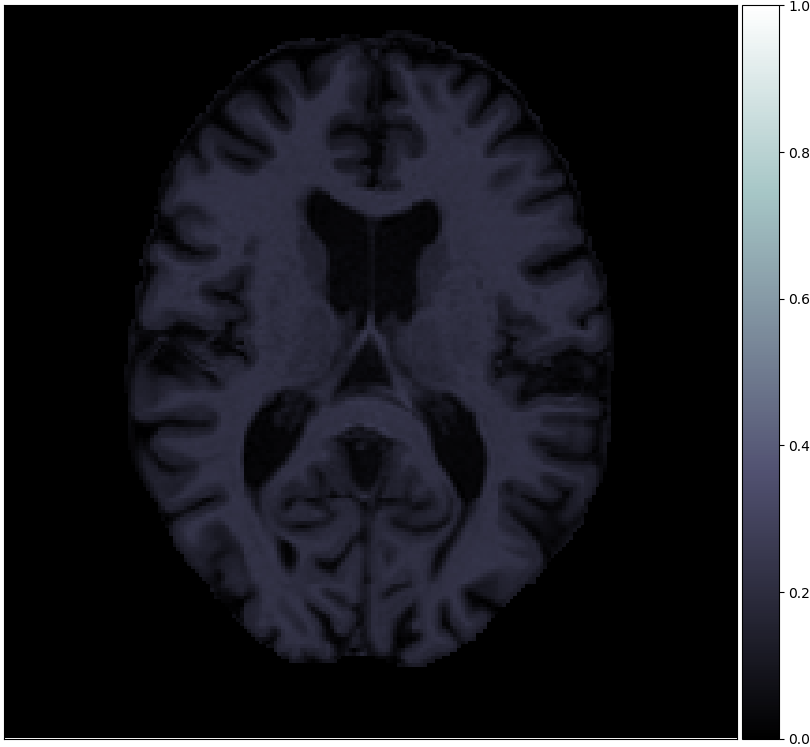

Figure 2 shows examples of each segmentation method on the MRBrainS13 data set, with Brainweb1.5T as the source center. For the unsupervised models we only show boundaries between clusters, to indicate that interpretation remains a necessary step. A couple of observations can be made: firstly, the hidden Potts models produce smoother segmentations. Secondly, the U-net over-predicts white matter in the whole image. Thirdly, the 1-nearest-neighbours classifier over-predicts background voxels in fluid regions. Lastly, all methods favour white matter over gray matter in ambiguous regions.